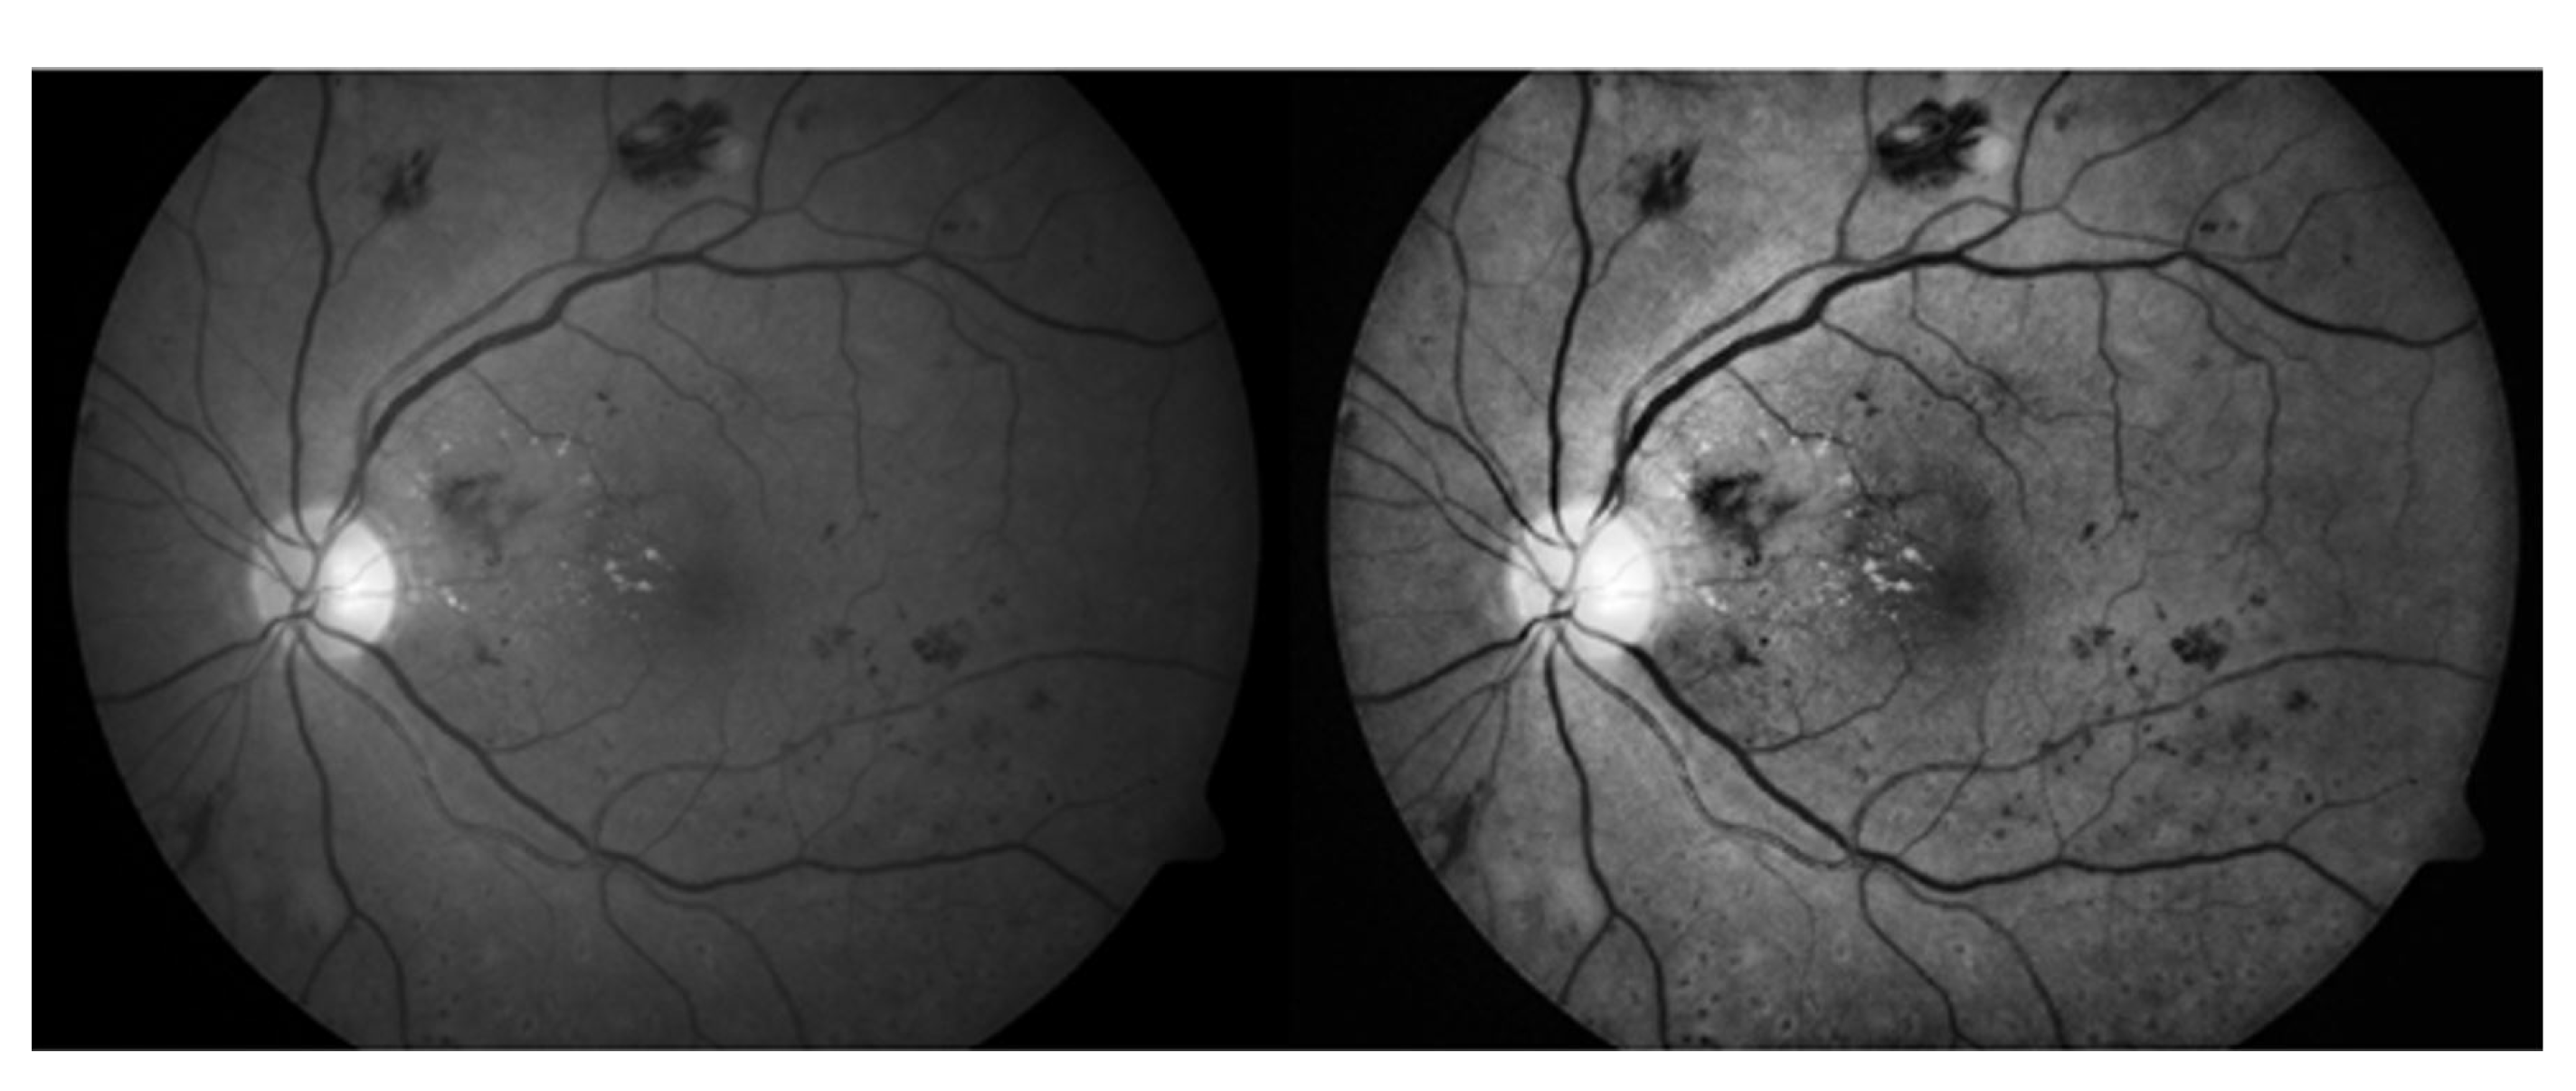

3.1. Green Channel Extraction

3.2. Contrast Enhancement

4.3. Results and Discussion